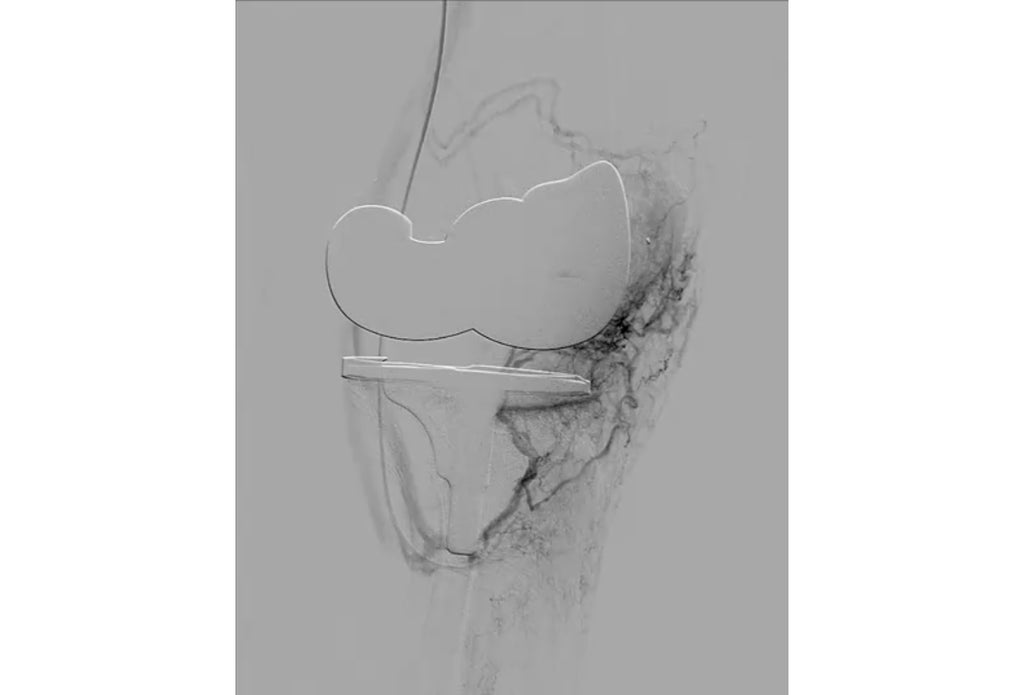

The procedure takes about an hour, and is performed by an interventional radiologist—a licensed physician who has undergone advanced training and obtained American Board of Radiology Certification to become a specialist in this field. An interventional radiologist uses X-rays and other imaging technology to see inside your body and to treat diseases without undergoing invasive surgery.

The interventional radiologist will insert a small tube into a groin artery that eventually supplies the knee. Then your doctor will use X-rays to guide the tube to the arteries surrounding the knee before injecting tiny particles (called microspheres) into smaller arteries that supply blood to the knee joint.

The result is less swelling in the synovium, the soft lining of the knee, while reducing inflammation of the joint.